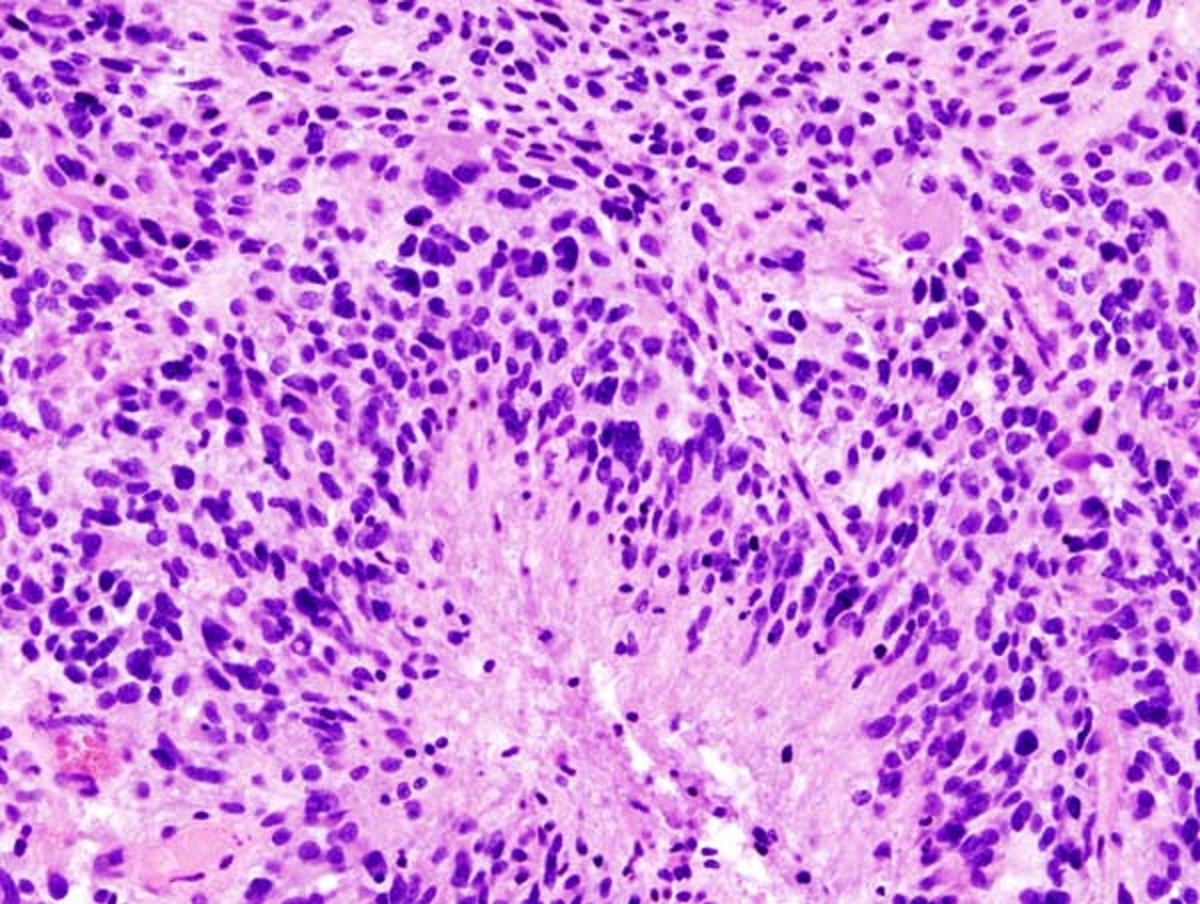

وتقدم الدراسة البحثية أملا جديدا وعلاجات محتملة للشكل الأكثر عدوانية من سرطان الدماغ: "الورم الأرومي الدبقي".

ثم فحص الباحثون نماذج لثلاثة أنواع مختلفة من السرطان، بما في ذلك الورم الأرومي الدبقي وسرطان "نقائل الرئة إلى الدماغ" وورم الأرومة النخاعية.